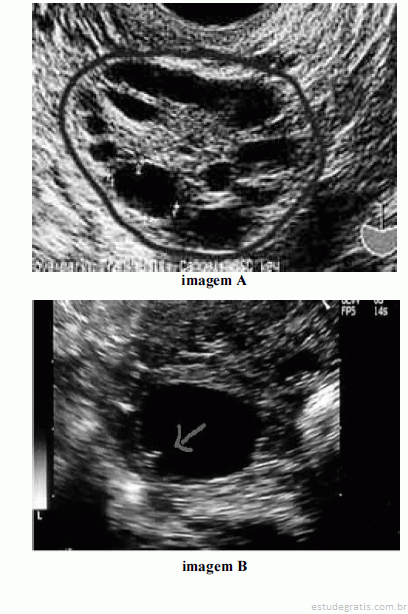

Considerando as imagens ovarianas apresentadas acima, julgue os itens a seguir.

Com base na imagem B, é correto afirmar que, muito provavelmente, ocorrerá ovulação em até doze horas.Comentários